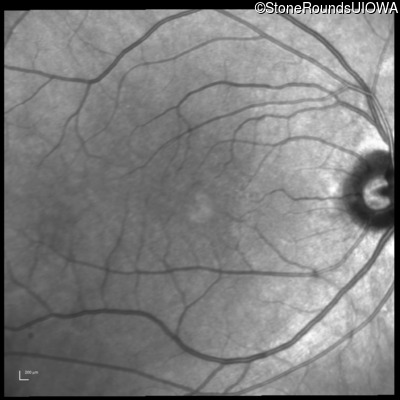

Infrared Fundus Photograph - Right - 20/20

Exemplar

Infrared Fundus Photograph - Left - 20/20 -2